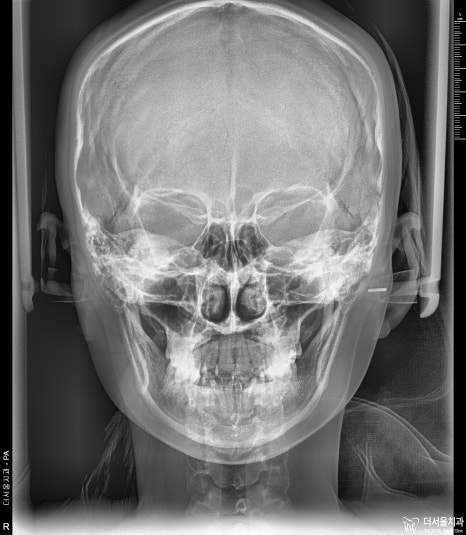

정면에서 볼 때는 앞니들의 배열 문제 이외에 돌출입 증세는 크게 느껴지지 않죠?

그리고, 안면 비대칭 또한 없는 분입니다. 이런 분들이 교정치료를 받으면 예후가 좋습니다.^^